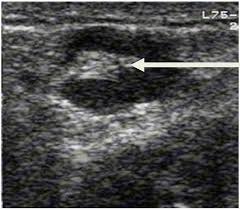

The person operating the ultrasound will sweep, or fan, the probe back and forth to look at different areas in 90 degree angle images. In addition, the following tests may be used to diagnose head and neck cancer: Cancerous lymph nodes can occur anywhere on the neck and are typically described as firm, painless, and sometimes may be immovable. In the normal neck, about 90% of nodes with a maximum transverse diameter greater than 5 mm will demonstrate an echogenic hilus on high resolution ultrasound. Symptoms of head and neck cancer can include:

Air and bone also reflect sound waves. A lump in the neck —cancers that begin in the head or neck usually spread to lymph nodes in the neck before they spread elsewhere. A neck ultrasound may help diagnose (find): Breast ultrasound images are seen from superficial (skin) to deep (chest wall muscle) over a segment of tissue. A neck ultrasound can be used to observe the thyroid gland to look for nodules, growths, or tumors. But now i am worried that the reason the lump didn't show on the ultrasound is because it is actually under the skin in my neck (i.e in my throat) rather than on my actual thyroid/neck. David dang answered 14 years experience radiology node, cyst or others: A small lump on the neck usually is a lymph node, a small sebaceous cyst or a lipoma, although it could be something else. The most common symptom of thyroid cancer is a hard lump on the neck—but most patients experience no symptoms at all. This means that they are larger than about 1 centimeter (about 1/2 inch) across. Optimal positioning and exposure of the neck for ultrasound of the thyroid and parathyroid glands (a, b) and lateral neck for lymph node examination and mapping (c).while the vast majority of patients are supine on the exam table with a pillow supporting the shoulders to allow gentle neck extension, keep in mind that some patients have beautiful anatomy (d) that allows ultrasound exam even in. 1), and the presence of an echogenic hilus within lymph nodes was previously considered a sign of benignity. What does a healthy kidney look like on an ultrasound?

A small device called a transducer is moved over the area. Optimal positioning and exposure of the neck for ultrasound of the thyroid and parathyroid glands (a, b) and lateral neck for lymph node examination and mapping (c).while the vast majority of patients are supine on the exam table with a pillow supporting the shoulders to allow gentle neck extension, keep in mind that some patients have beautiful anatomy (d) that allows ultrasound exam even in. The camera remains attached either to a flexible tube called endoscope or to a probe, while it passes within an opening in your body, often your mouth. In the normal neck, about 90% of nodes with a maximum transverse diameter greater than 5 mm will demonstrate an echogenic hilus on high resolution ultrasound. Ultrasound an ultrasound is sometimes used, especially to look at the thyroid, salivary glands and lymph glands in the neck. A neck lump or nodule is the most common symptom of thyroid cancer. Should your doctor suggest that you undergo a neck ultrasound, you can be confident that your scan will be conducted by highly trained, experienced and caring sonographers. But now i am worried that the reason the lump didn't show on the ultrasound is because it is actually under the skin in my neck (i.e in my throat) rather than on my actual thyroid/neck.

Breast ultrasound images are seen from superficial (skin) to deep (chest wall muscle) over a segment of tissue. These are frequently seen in nodules containing papillary thyroid cancer. A 'neck check' is a simple procedure that can be done just about anywhere. 1), and the presence of an echogenic hilus within lymph nodes was previously considered a sign of benignity. David dang answered 14 years experience radiology node, cyst or others: